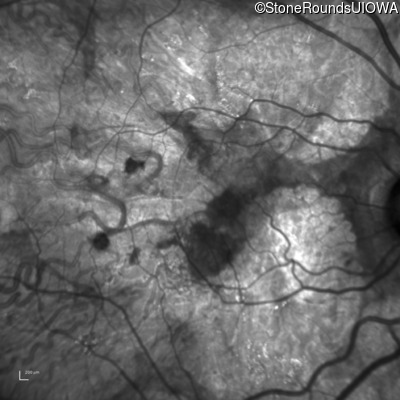

Age at visit: 54 years

Age at visit: 54 years (Visit 2)